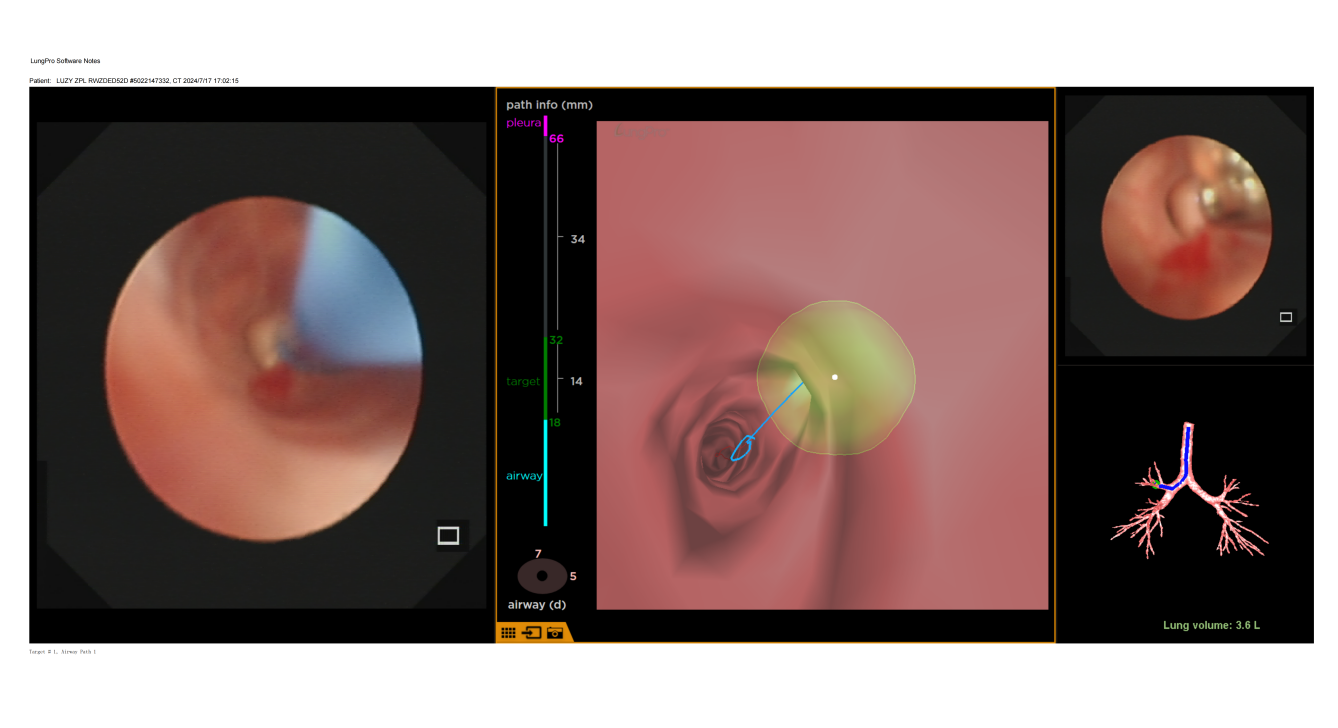

术前,介入团队对患者胸部 CT 进行 LungPro3D 重建,详细描绘出结节、周围血管、邻近支气管的相互位置关系,规划出了一条可以避开血管的相对安全、路径最短的穿刺路径。

在麻醉与围术期医学科的全力支持下,叶小群为患者实施了 LungPro 导航下 BTPNA 术。在导航引导下,支气管镜在 10 分钟内到达病灶位置,叶小群采用一次性支气管镜穿刺活检套装进行穿刺、扩张及鞘管置入,建立 1 cm 隧道后,经超声确认位置理想,立即使用活检嵌顺利取得病灶组织,患者无出血及气胸等并发症。经病理确诊,患者为宫颈转移性腺癌。